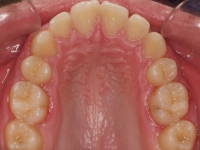

La paciente O.O. acude a nuestra consulta por:

– Canino 13 e incisivo lateral 42 en posición ectópica.

– Canino 23 incluido.

Con lo que decide realizarse un tratamiento de ortodoncia de duración de 24 meses con brackets damon Q.

CASO COMPLETO: